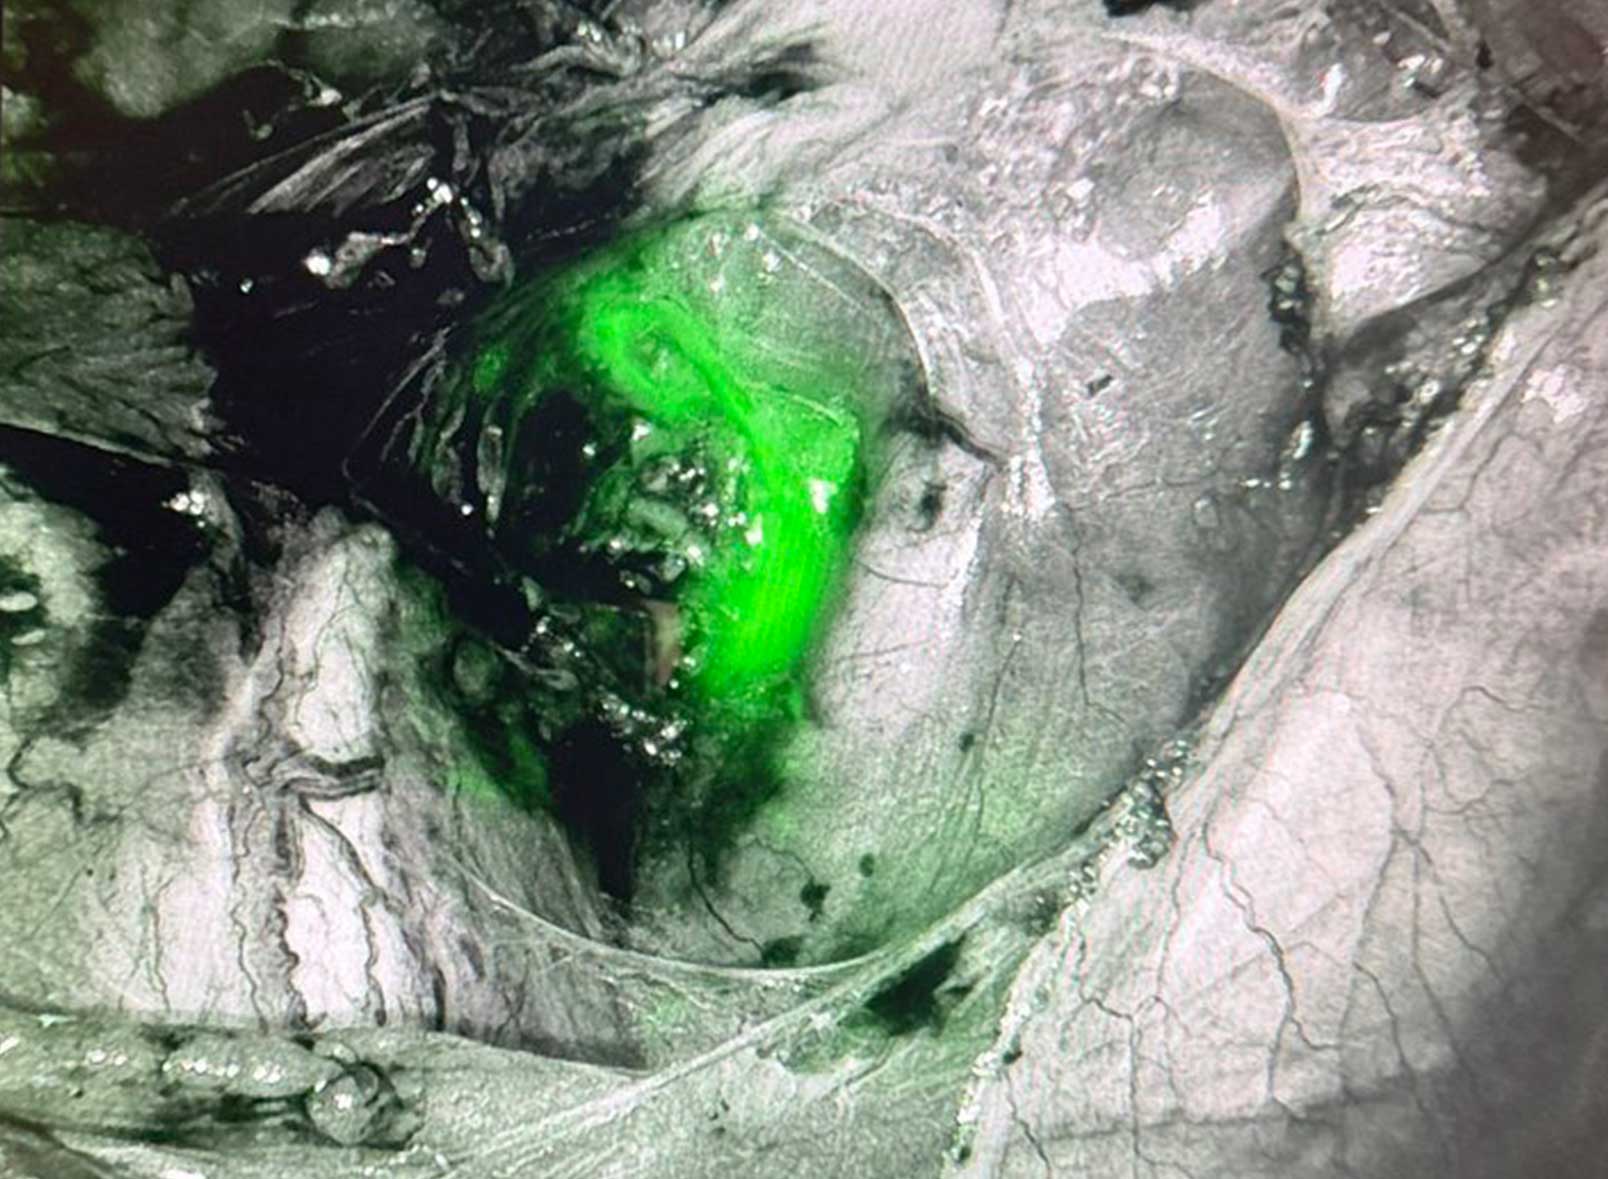

子宮悪性腫瘍に対するセンチネルリンパ節生検

子宮悪性腫瘍手術における骨盤リンパ節郭清は、病期決定に重要である一方、下肢リンパ浮腫などの合併症を来すことがあり、 リンパ浮腫は難治性でQOLを大きく低下させる場合があります。

センチネルリンパ節とは、がんが最初に転移すると考えられるリンパ節です。 センチネルリンパ節に転移がなければ、系統的なリンパ節郭清を省略できる可能性があり、 腫瘍手術の根治性を担保しながらQOLの維持を目指す低侵襲な治療戦略です。

当科では2024年10月より導入し、2025年12月までに13件の実績があります。

センチネルリンパ節(緑色)